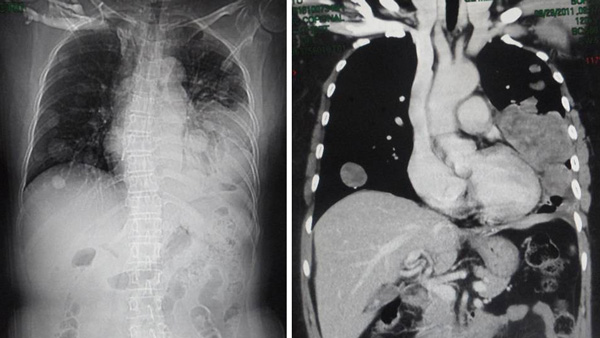

a) … do not allow your doctor to over-test your body with excessive amounts of radiation including excessive CAT scans or PET Scans, which can often make your condition worse by weakening your immune system (page 31),

b) … a single CAT Scan of the chest may be equivalent to 100 plain chest X-ray films and a PET scan performed with a radio-tagged sugar molecule may deliver 5 times the radiation dosage and exposure of a single CAT Scan(page 100),

c) The” gold standard” and most invasive testing is that of the PET Scan, which by radiological standards delivers as much radiation to the recipient as the entire combination of a head, chest, abdomen, pelvis and home scan combined (page 34),

d) The PET scan is based upon the fact that cancer cells, out of necessity rely upon simple sugars for this main source of nutrition. The scan itself uses a radio-tagged sugar molecule to essentially “light up” cancer anywhere in the body, except in the brain tissue which also rely upon sugar as its main source of energy. (page 34),

e) Incidentally, the PET scan is not definitive by any means. A cancer deposit or metastasis must reach a diameter between 5.0 and 10.0 mm before it can even be detected on a PET scan. Therefore, a sizeable amount of cancer could be present in the body and not be detected at all on PET scanning (page 35).